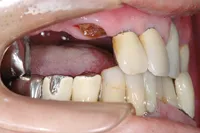

インプラント治療及び補綴治療のケース

■治療前:奥歯が無いため噛み合わせが深く下の歯が全く見えない

噛み合わせが低いため全体的に歯が削れている

■治療後:下顎 左下5・6番、右下4・6番にインプラント治療

その他の歯に補綴治療をしたことにより、奥歯もしっかりと咬むことができ、奥歯ができたことにより噛み合わせも上がって下の歯も見えるようになり、審美的にも改善された

| 主訴 | 歯科治療をしても歯がすぐに欠けてしまう 奥歯が無いため、奥歯で咬めない |

| 治療方法 | インプラント治療 + 補綴治療 |

| 治療期間 | 約1年 |

| 通院回数等 | 約20回 |

| 費用 | 約250万円(税込) |

| リスク・副作用 | 術後の腫れ・痛み |